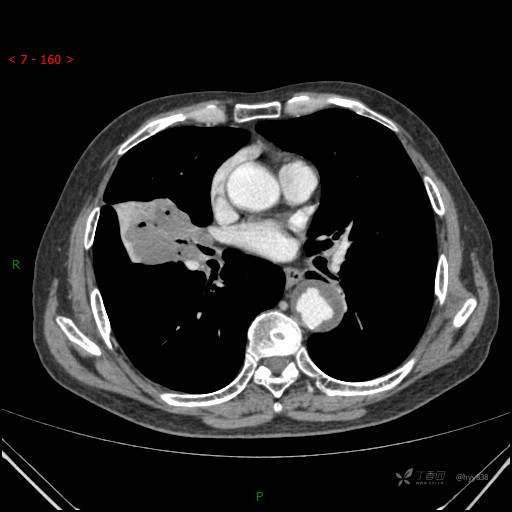

静脉期

增强动脉期